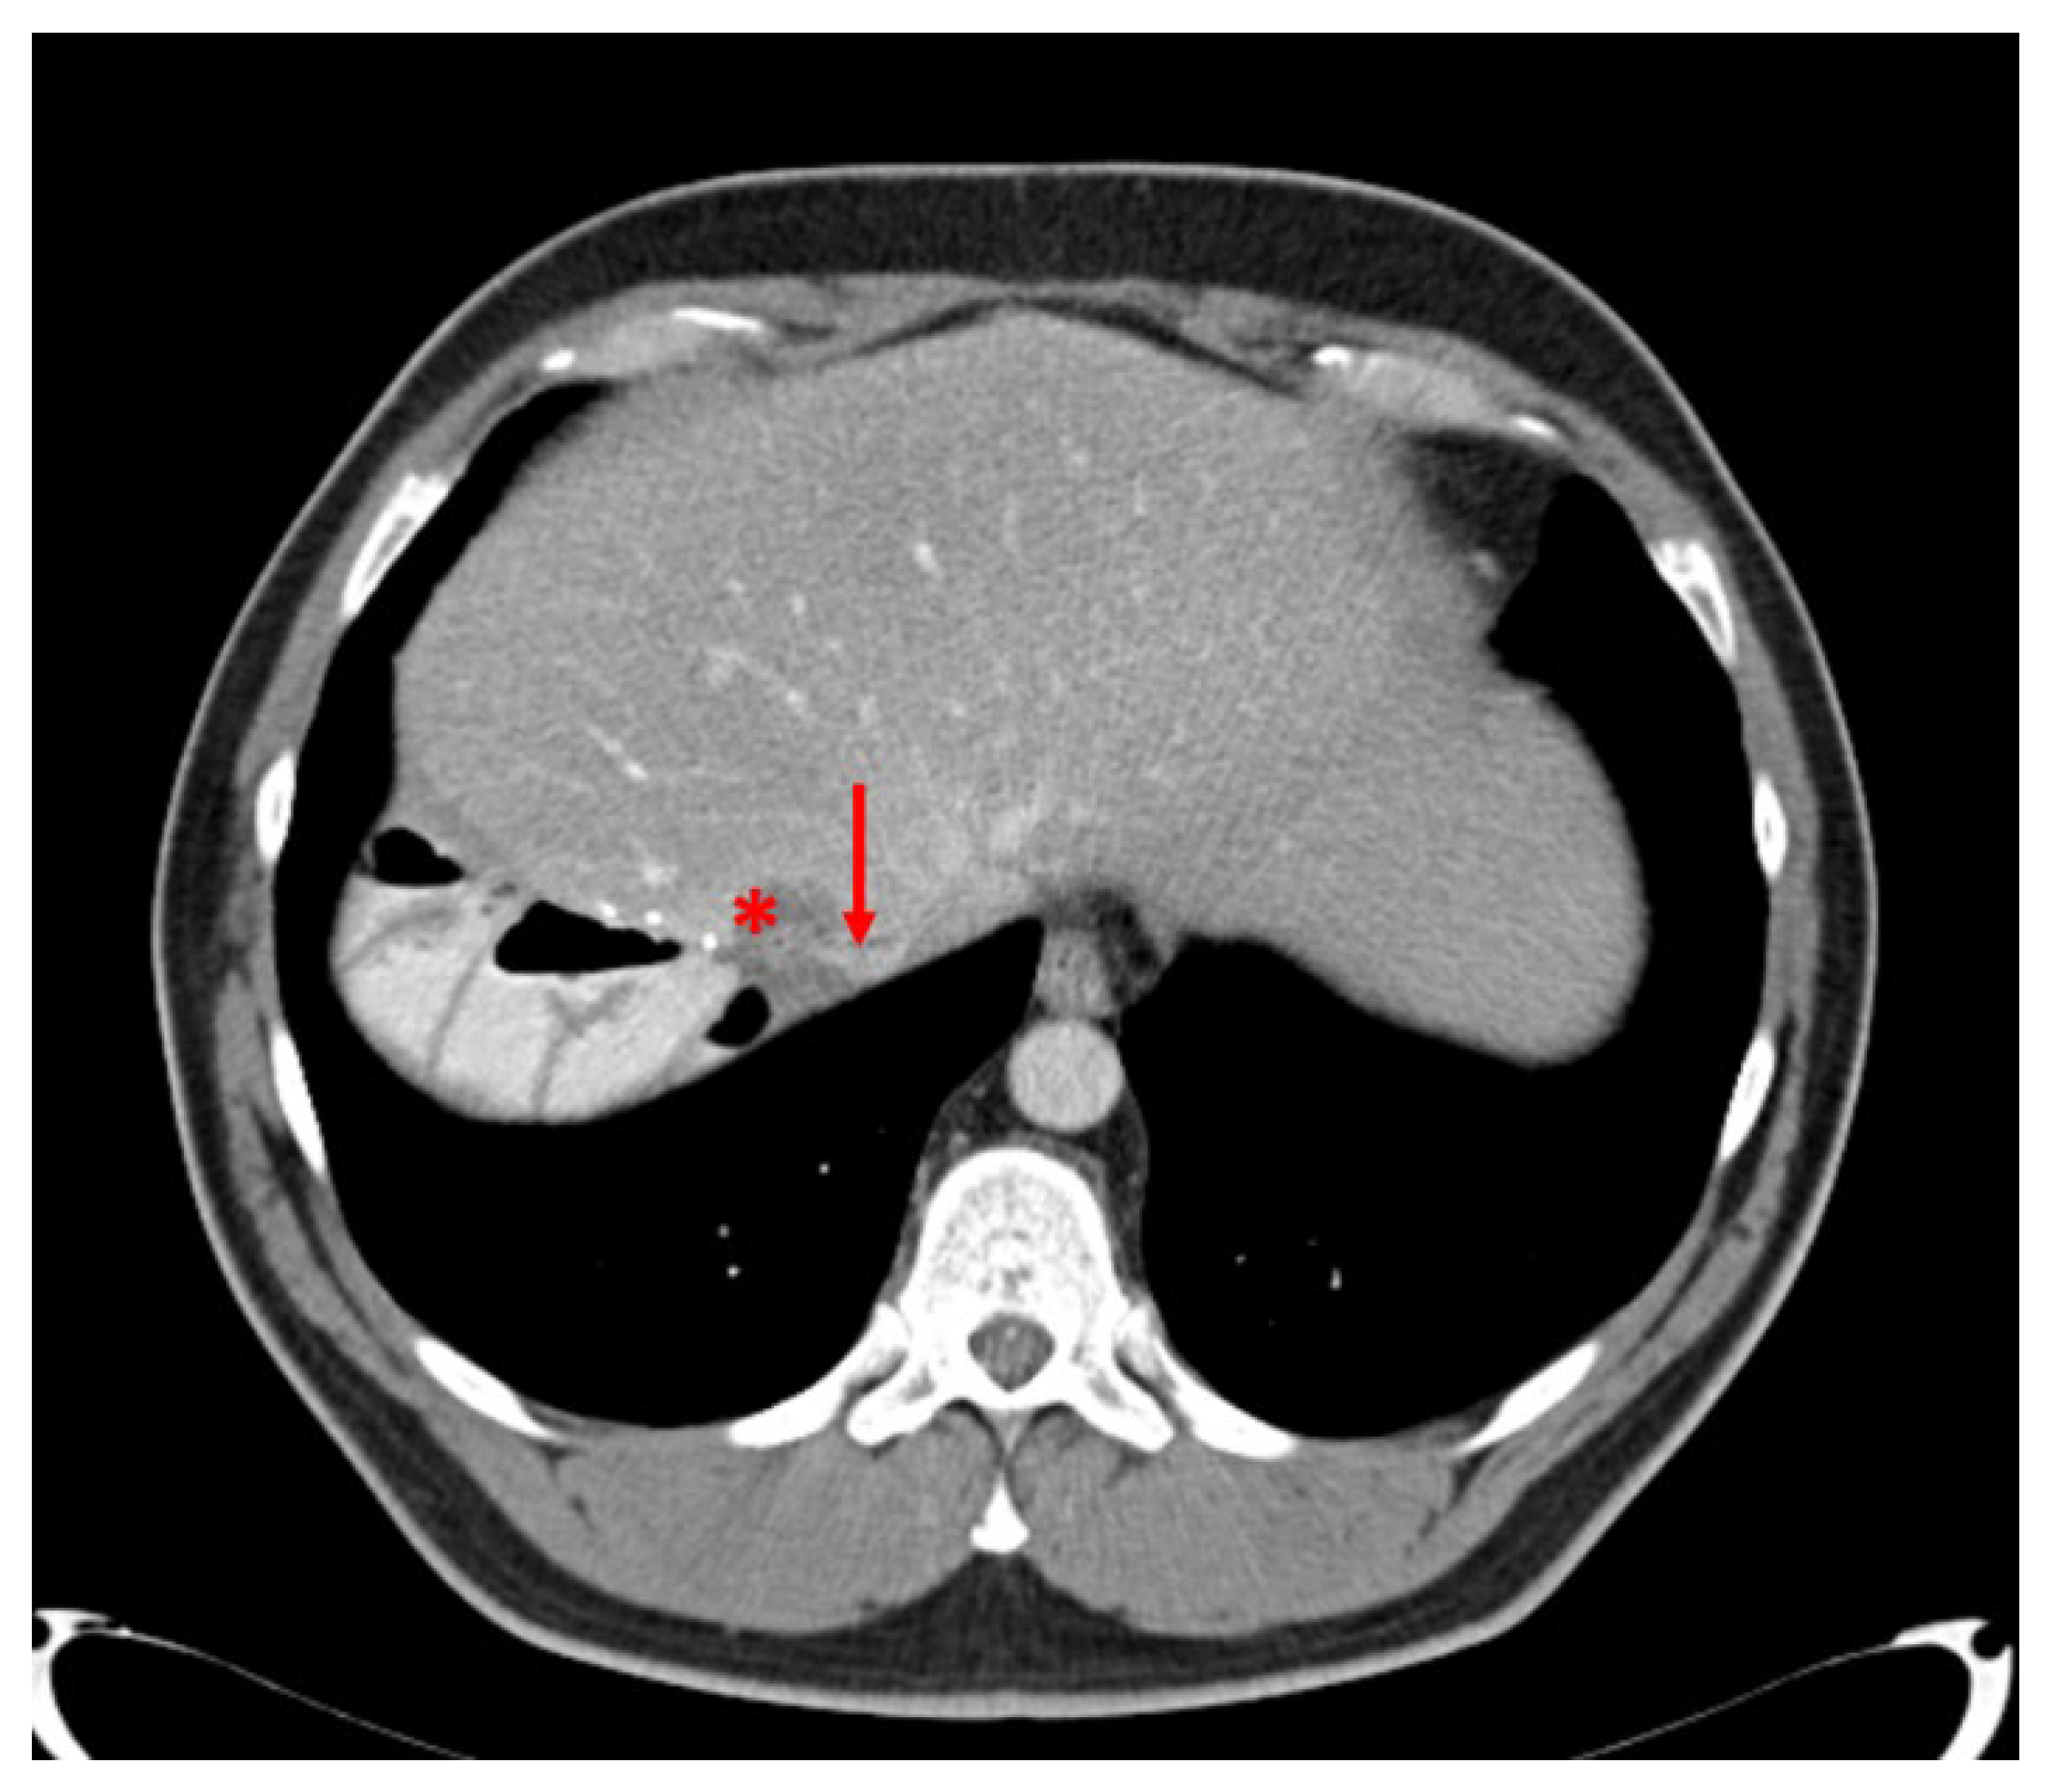

3.6. Case Report 1

3.7. Case Report 2